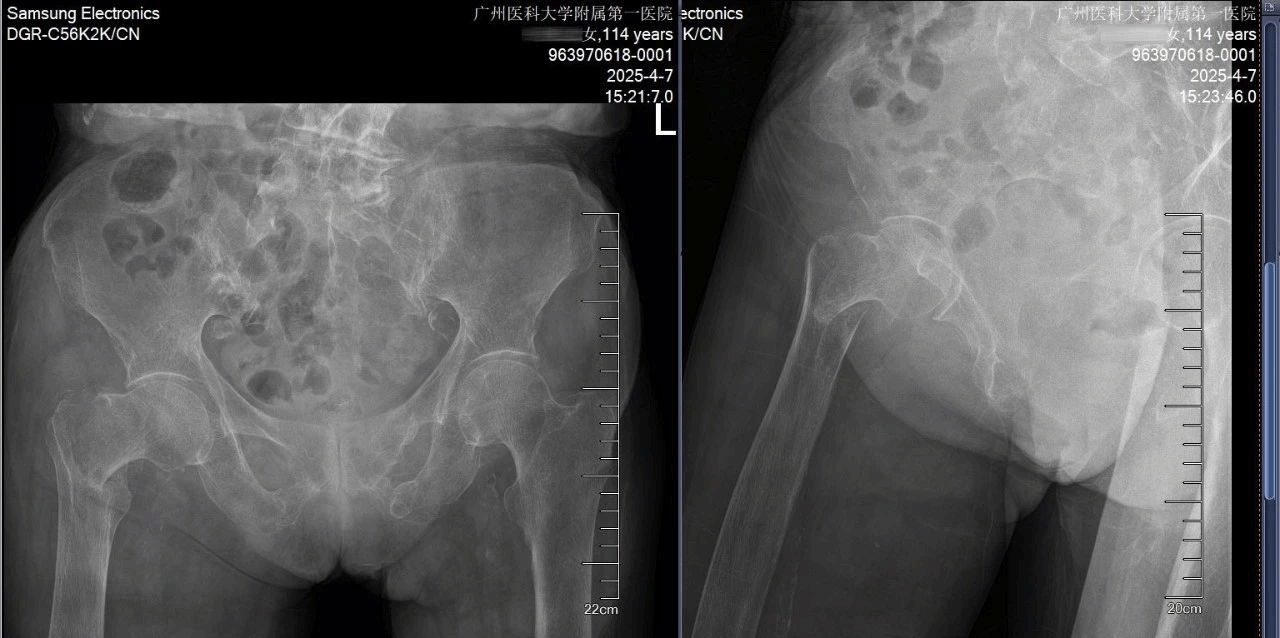

术前全面评估,患者术前有下肢DVT、肺部感染、慢性心功能不全、中度贫血、低蛋白血症,X线片显示股骨皮质极薄、股骨髓腔呈“烟筒样”改变。术前多学科会诊并给予抗凝、控制肺部感染、改善贫血和低蛋白血症、治疗骨质疏松、改善心功能,为麻醉、手术治疗创造条件。

术前术后X光照片